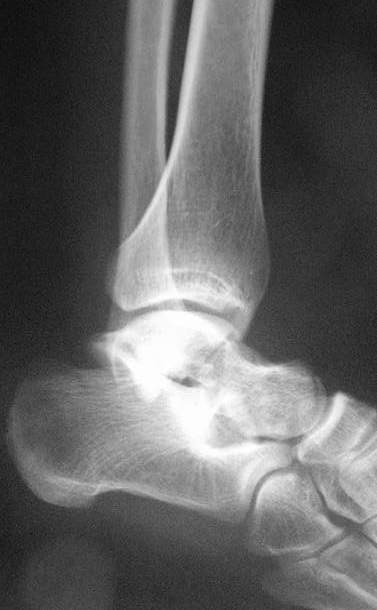

3 дня назад поступила пациентка  23 года с переломом шейки ладьевидной

справа, переломом лодыжек заднего края б/берцовой кости со смещением и

подвывихом кзади, переломом внутреннего мыщелка правого бедра без смещения.

Дежурными хирургами проведена репозиция в левом г/ст суставе успешная,

попытка репозиции таранной кости ухудшило положение отломков.